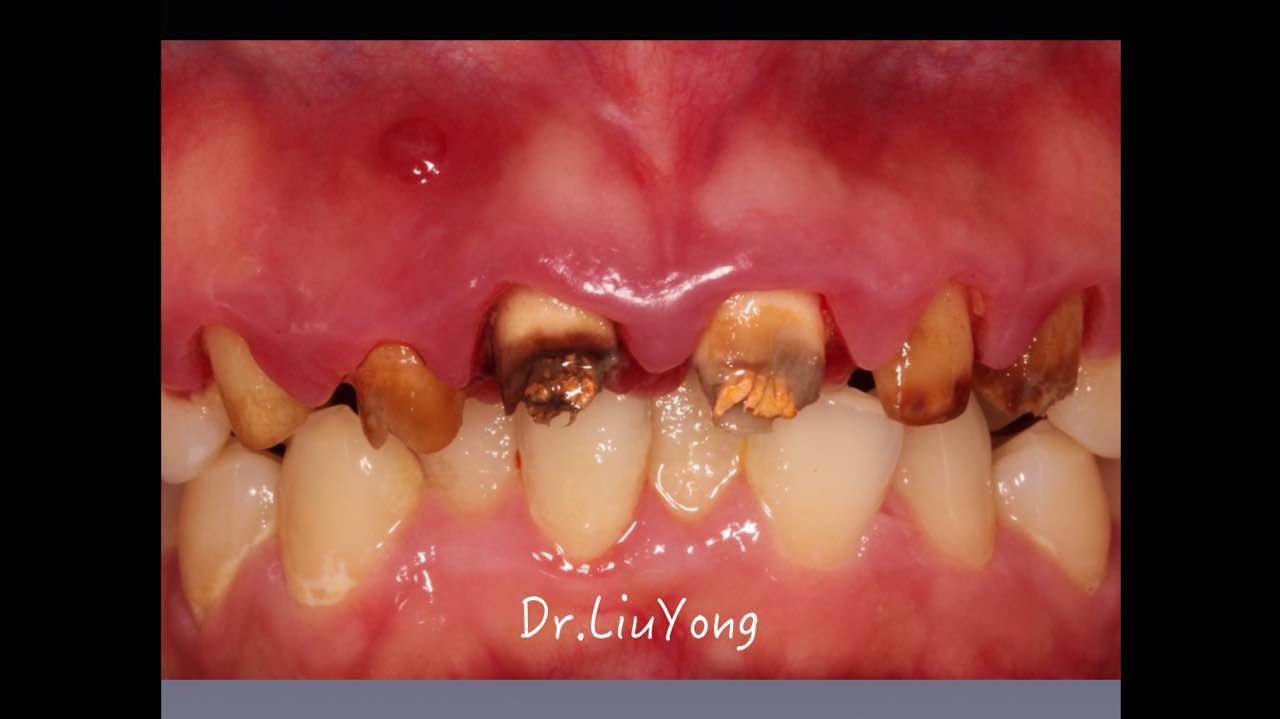

嚴(yán)重破壞生物學(xué)寬度,根尖瘺管,重行根管治療, 第一次冠延長建立唇腭側(cè)及鄰面BW,術(shù)后牙齦扇貝形差, 齦乳頭黑三角,再次行美學(xué)冠延長,建立牙齦扇貝形,手術(shù)免費, 患者因經(jīng)濟原因只能選擇鑄樁及鈷鉻合金烤瓷冠。終于完工